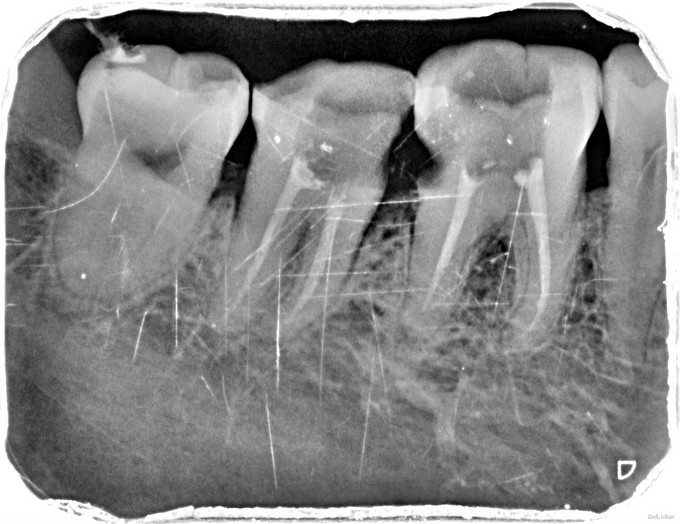

临床检查:46,47邻面龋坏,探(+),冷(++),叩(-),松动度(-),牙周正常. 35,36残冠,15,16,25缺失。 辅助检查:X线示46,47龋坏累积髓腔,36龋坏深达根分叉处。

诊断:46,47牙髓炎,35,36残冠。 治疗:经患者知情同意后,46,47局麻去腐降牙合,开髓拔髓寻找根管口,建立直线通路,扩通根管,确定工作长度。S3/EDTA凝胶镍钛器械,低浓度次氯酸钠冲洗根管,预备至35/04,氢氧化钙诊间封药,患者符合拔牙适应症,拔除35,36.一周后复诊,试主尖X线示恰充,试干根管,导AH-PLUS糊剂,VDW热压胶垂直加压根充,术后见根管恰充,暂封调合抛光。观察一周桩冠修复。